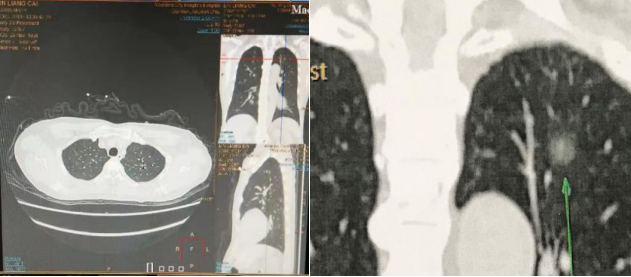

据了解,患者林叔(化名)在体检时发现左上肺多发微小结节后,立刻到我院胸外科就医,该科专家了解患者病情病例后,组织院内肺结节MDT团队讨论,MDT团队专家认为位于左上肺尖后段毛玻璃样结节(GGO)未排除肺癌可能,且肺外周还存在2个微小结节,目前常用的术中定位方法为手指触摸,但对于GGO术中触摸成功率低,而目前广泛使用的术前Hookwire定位方法,虽然成功率高,但经皮肺穿刺容易造成气胸、血胸等并发症。同时,考虑到患者年纪比较大,因此考虑开展新技术——“电磁导航支气管镜技术联合荧光胸腔镜下微创精准切除肺结节术”。在与患者及家属沟通后,胸外科团队为该患者详细制定诊断及手术治疗方案,并联合呼吸与危重症医学科一区及麻醉手术科开展手术。

我院呼吸与危重症医学科一区专家团队利用电磁导航支气管镜精准定位,在麻醉医师的协作下,胸外科手术团队成功完成了荧光胸腔镜下左肺S1+2段切除+左上肺楔形切除术,较大限度地保留了患者的肺功能,患者术后恢复良好,术后病理确诊GGO为原位癌。

据胸外科主任黄健介绍,电磁导航支气管镜技术采用三维CT重建技术和电磁定位原理,可引导支气管镜及电磁定位导管准确到达肺内病变所在,建立工作管道,以便准确对病灶进行标记、活检或微创介入治疗,且经自然腔道导入无体表损伤。通过利用导航系统进行荧光标记,精准确定病灶位置,使病变质地与正常组织质地相区分,提高了肺部肿瘤手术的安全性和准确性,减少不必要创伤的同时,为患者完整切除肺部结节并提供准确的病理诊断。